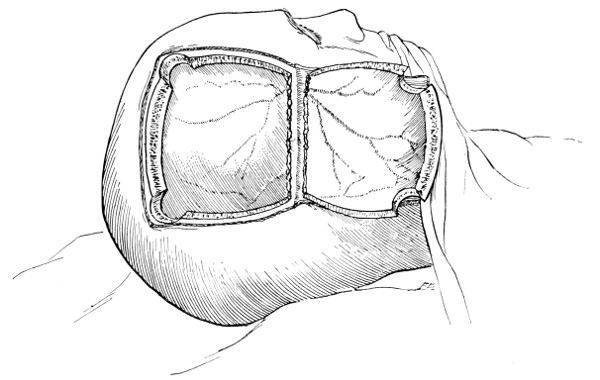

Fig. 18. Second Stage in the Formation of an Osteoplastic Flap. The bone-flap turned down and the dura mater exposed.

Fig. 19. Third Stage in the Formation of an Osteoplastic Flap. The dural flap turned down and the brain exposed. Note the relation of the scalp, bone, and dural incisions to one another.

The dura is now separated from the bone along the line of the two vertical incisions, and the visceral blade of de Vilbiss’s forceps insinuated beneath the bone, starting at one trephine-hole and working downwards to the lower limit of the incision. It is essential that the operator should be satisfied with the ‘morcellement’ of small portions of bone at each bite of the instrument. At the lower end of each[28] of the vertical incisions the forceps is directed inwards for 1⁄4 to 1⁄2 inch so as to weaken the base of the flap.

To lift up the osteoplastic flap, a stout elevator or spatula is introduced beneath the bone at its upper part, leverage applied, and, as soon as sufficient elevation has been attained, the dura mater carefully separated from the whole of the under aspect of the flap. The flap is then grasped at its upper part with both hands and, with a quick but forcible jerk, broken across at its base, the assistant at the same time aiding the correct linear fracture of the bone by a flat spatula applied to the outer aspect of the base of the flap. Insomuch as the flap is most usually framed in the parieto-temporal region—for the exposure of the motor area—the base of the flap, being formed from the squamous portion of the temporal bone, is comparatively weak. Fracture is then readily obtained. Under other circumstances the base may be sufficiently weakened by the application of the de Vilbiss forceps or by the use of the Gigli saw.

The bone-flap is thrown back and enveloped in gauze. Its basal region is examined for a possible injury to meningeal vessels. In the event of such complications the bleeding vessel is clipped, ligatured, or underrun. Possibly some branch of the anterior division of the middle meningeal artery, running in an osseous canal, may require to be controlled by foraminal occlusion—with a wooden match, bone peg, cotton-wool, or aseptic wax.

In comparing the relative advantages and disadvantages of craniectomy and craniotomy, although there are certain definite contra-indications to the latter method, yet craniotomy should always be carried out when the surgeon desires to expose a large surface area of brain, more especially in the exposure of a tumour diagnosed to lie in relation to the motor cortex. Even if the operator should be unsuccessful in his exploration, or, if finding the tumour, should deem it irremovable, the dura can be sewn up and the bone-flap replaced, resting on its bevelled edge, with little defect in the skull and a normal surface contour.

The three main disadvantages to craniotomy are as follows:—(1) the operation can seldom be done under much less than thirty minutes; (2) there is some slight risk of complication through injury to the middle meningeal artery; and (3) the dura mater may be so[29] adherent to the bone as to be torn in the process of flap-elevation. Time, however, is usually of little importance; bleeding from the middle meningeal artery may be controlled, and dural lesions may be avoided by careful technique. In general, the advantages of osteoplastic resection greatly outweigh the disadvantages.